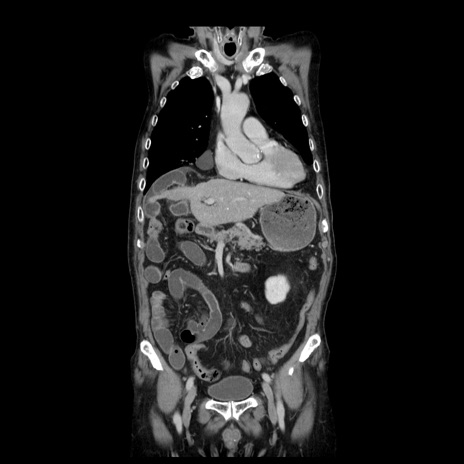

症例21(冠状断像)

【症例】70歳代男性

【主訴】腹痛

【現病歴】肝硬変・肝細胞癌にてかかりつけの方。約9時間前に食後より腹痛出現。症状が徐々に増悪し、嘔吐出現したため来院。

【既往歴】肝硬変、肝細胞癌(RFA、TACE後)

【身体所見】意識清明、表情苦悶様、BT 36℃、BP 129/78mmHg、P 88bpm、SpO2 97%(RA)、右上腹部から心窩部にかけて圧痛あり、反跳痛なし、筋性防御あり。

【データ】WBC 5800、CRP 0.16